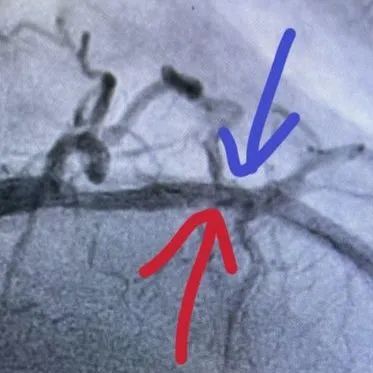

术中连续治疗8个周期(80次脉冲)后,复查OCT可见钙化处内膜至支架梁间的明显裂隙,震波深度达0.49mm,钙化环被打开。换用3.0×15mm NC高压球囊18-20atm充分扩张。

术后运用OCT测量评估,MSA恢复到4.86mm²,治疗前后造影对比,病变扩张满意,支架内狭窄基本消失,TIMI血流3级,患者无不适主诉。